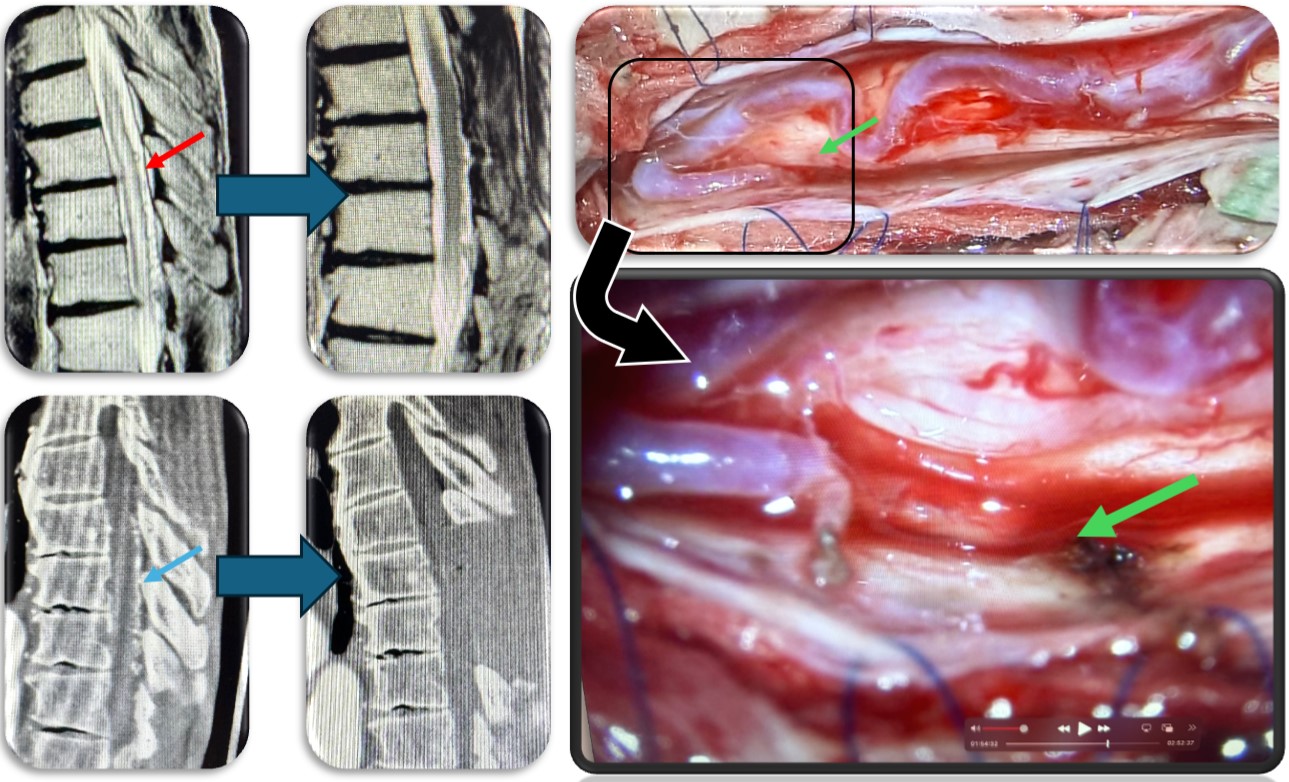

硬膜動静脈瘻の症例です。脊髄血管奇形の中では最も多い疾患です。脊髄の静脈に動脈血流が直接流入する事により脊髄浮腫をきたし(赤矢印)、様々な神経症状が出ます。最近では血管内から治療することもありますが根治率は20%程度と非常に低く、基本的には高い確率で根治できる外科的治療を施します。当院では基本的には外科的治療を選択しますが、高齢者や外科的治療が困難な症例では血管内治療を検討することもあります。手術では動脈から静脈に直接流入する部位(緑矢印)を焼灼離断します。術直後に脊髄浮腫は改善し、造影CT検査で描出の認めた異常血管影(青矢印)は術後に消失しました。